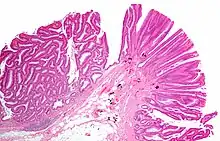

Normal (left) versus dysplastic (large at right) colonic crypts, the latter conferring a diagnosis of a tubular and/or villous adenoma.